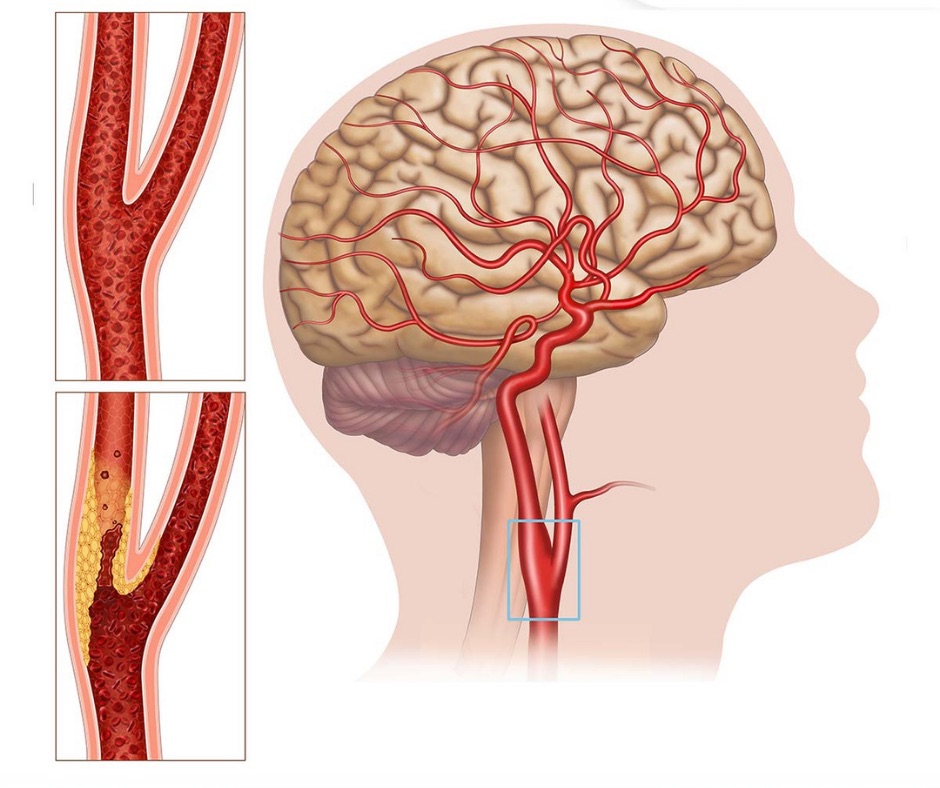

🩺 2. Plak Varlığı

- Şah damarlarında plak olup olmadığı kontrol edilir.

- Mevcut plakların yerleşimi belirlenir.

- Genel görünümü ve yaygınlığı incelenir.

Erken Teşhis

Damar sertliğinin erken evrede saptanması.

Risk Öngörüsü

İnme ve kalp-damar hastalıkları riskinin öngörülmesi.